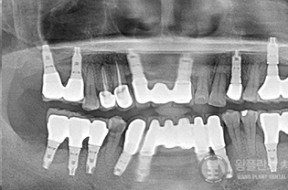

전후사례